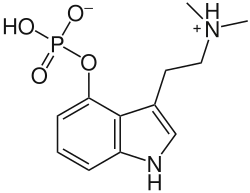

Chemical structure of psilocybin, the main active constituent of psilocybin-containing mushrooms and one of the most well-known hallucinogens. | |